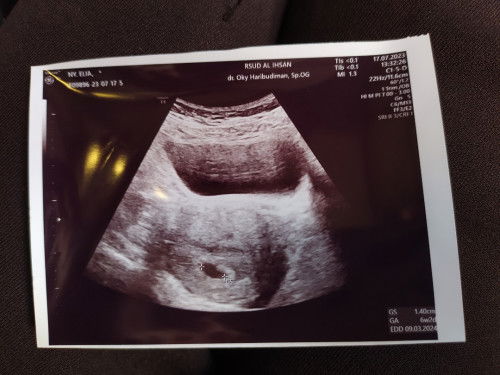

BELUM TERLIHAT JANIN USIA 6 MINGGU

#pleasehelp moms.. ini usg kehamilan aku usia 6 Minggu kata dokter. Itu keliatan kantong janin nya kecil, tapi digambar kayaknya ga terlihat janin. Dokter nya bilang kalau usia segini memang masih item2 gajelas, nanti setelah beberapa2 Minggu lagi USG baru bisa terlihat janinnya. Tapi aku penasaran mom, dan juga sedikit khawatir, kadang suka overthinking takut terjadi apa2 kalau janin ga langsung keliatan :( Apakah hal ini wajar moms ? Aku baru mau USG 2 mingguan lagi.. huhu